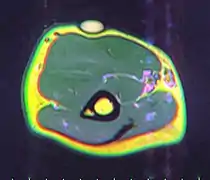

A physical exam is typically the easiest way to diagnose it. Rarely, a tissue biopsy or imaging may be required. The imaging modality of choice is magnetic resonance imaging (MRI), because it has superior sensitivity of distinguishing it from liposarcoma as well as mapping the surrounding anatomy.[20]

MRI showing lipoma of the arm